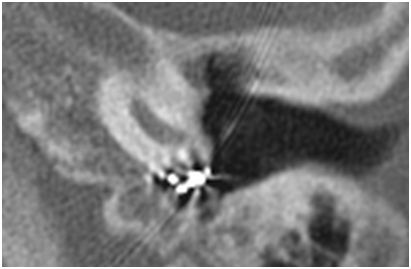

Cases of the extrusion

There was electrode array extruding through posterior canal wall 9 years after implantation in first case (Figure 1). It was founded an injury of the posterior wall at the posterior tympanotomy, an epidermis growth over the surface of the electrode in the mastoid cavity during revision surgery. It was performed the electrode extraction, sanitation mastoid cavity, reinsertion of the same electrode and a cartilage electrode covering. There was an electrode extrusion through the tympanic membrane and labyrinthitis in second case. It was founded an injury of the annulus fibrosis. We performed an electrode extraction and tympanoplasty. In 3th case, the extrusion of the electrode array was due to the inflammation in the middle ear caused by Pseudomonas aeruginosa. Explantation and tympanoplasty was performed.

Figure 1 Otoscopic view ‒ electrode array extruding through posterior canal wall 9 years after implantation.